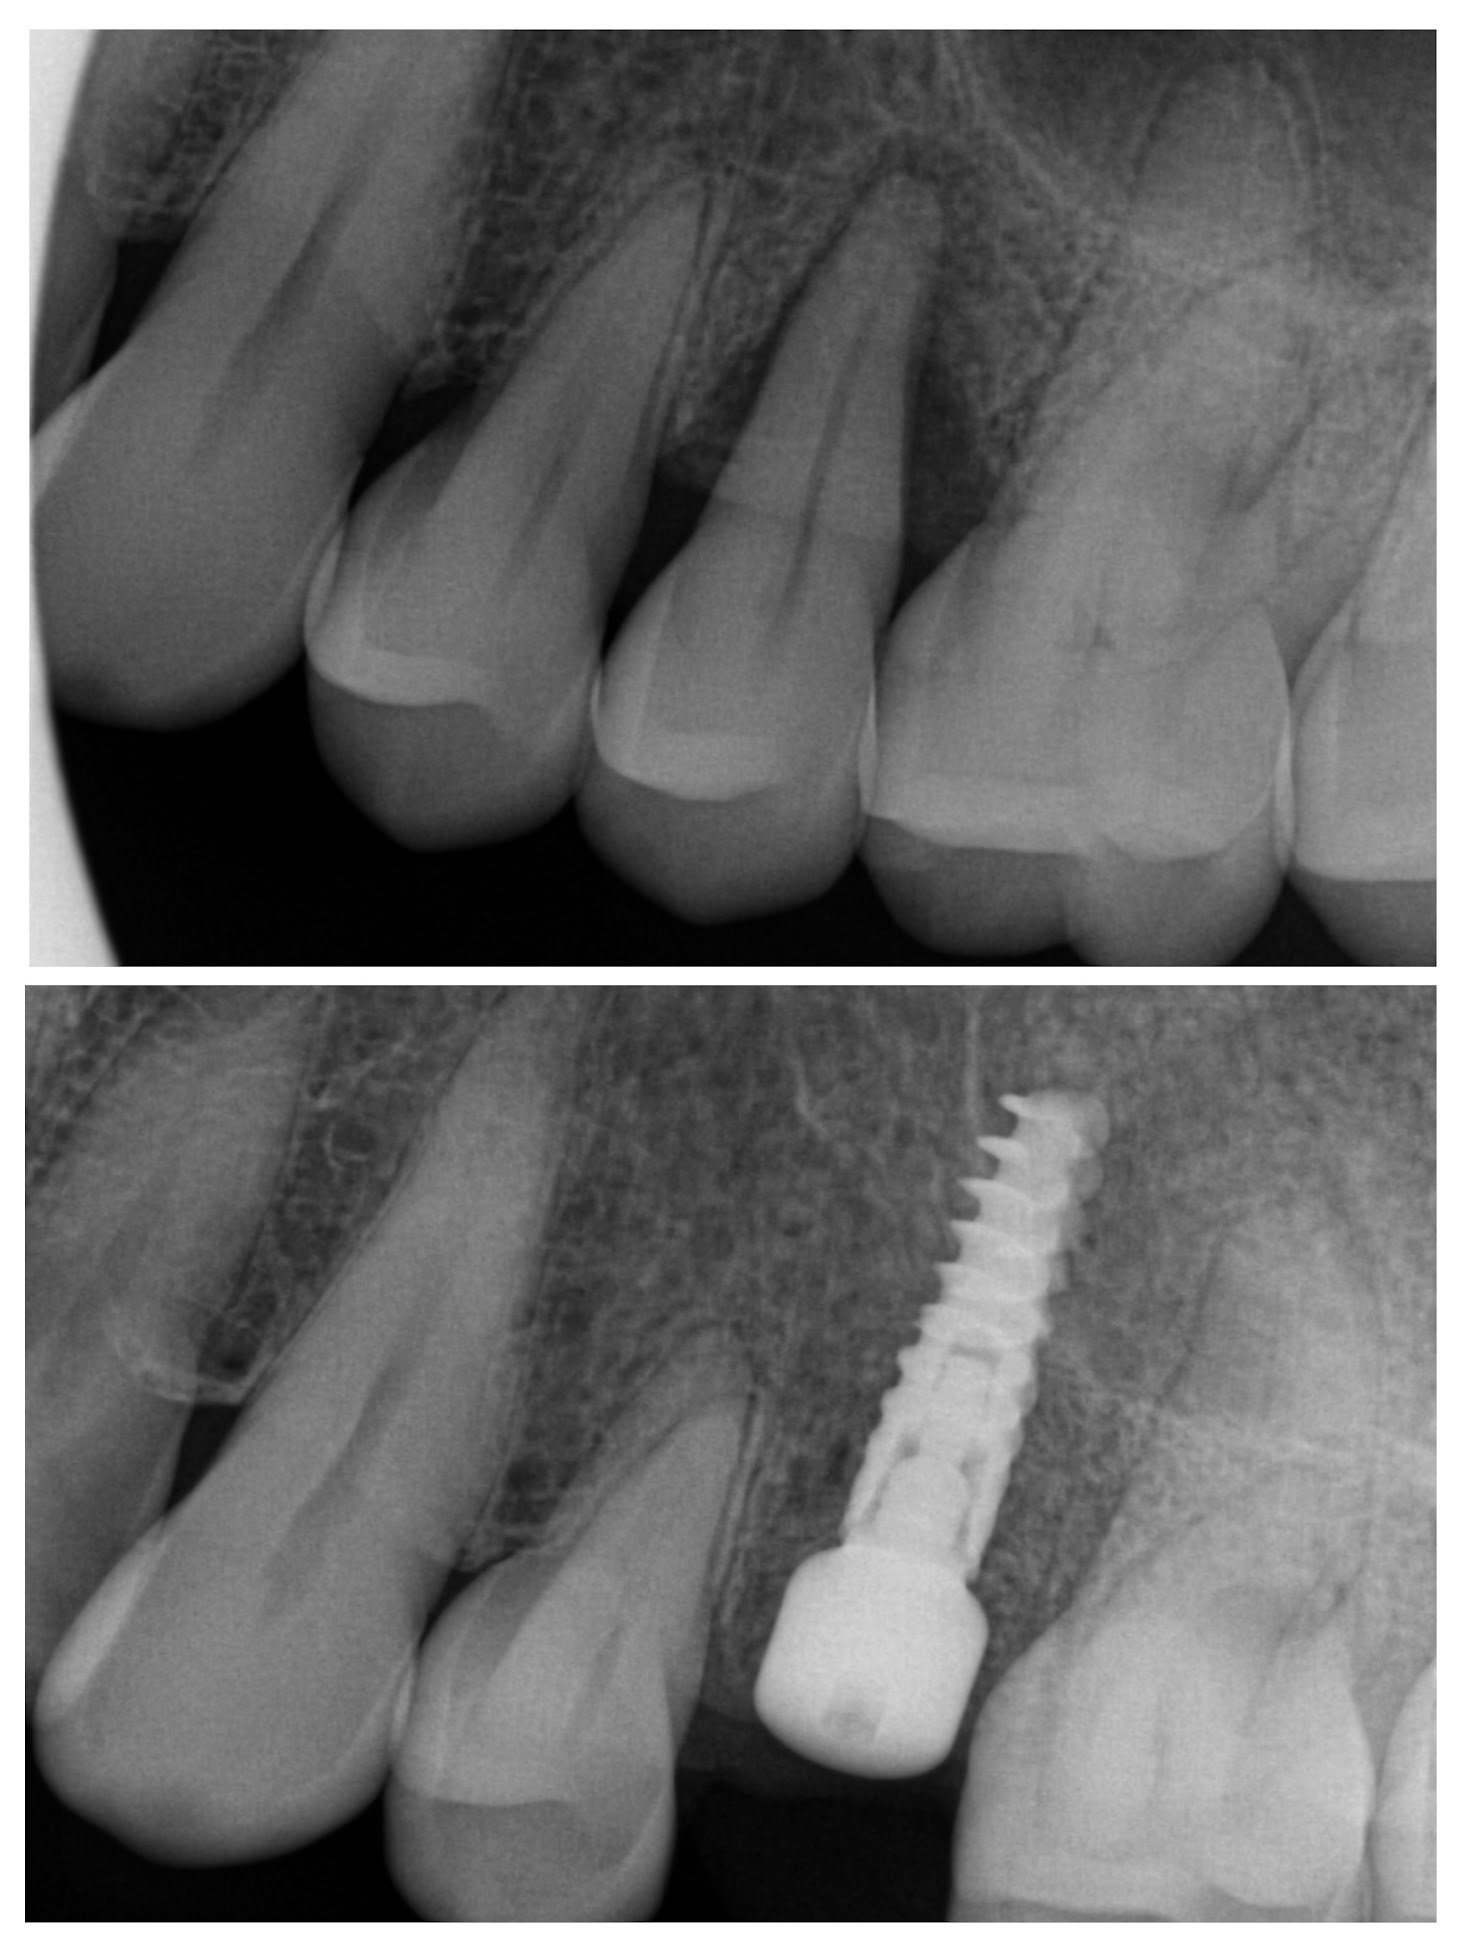

Dental Implants

With the newest technology and products, we can provide a predictable solution for tooth loss.

Implant planning

Implant placement

Extraction of tooth and placement of immediate implant

Implant Planning with CBCT imaging